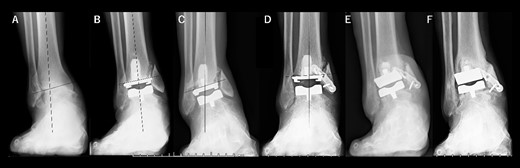

A 75-year-old woman with end-stage ankle OA and severe ankle joint pain and gait dysfunction had a JSSF ankle/hindfoot scale score of 42 points. Talar tilt showed 21° varus (Fig. 3A). She underwent TAA with medial malleolar osteotomy without internal fixation, and the tibial component was placed in the 4° valgus position, unlike the other two cases (Fig. 3B). At present, 5 years after TAA, she can walk for more than 2 hours and feels no pain around the ankle. There is no evidence of prosthesis loosening even though incomplete bone union at the osteotomy site is evident (Fig. 3C).

Radiographs of preoperative weight-bearing radiograph of the antero-posterior ankle joint in Case 3. (A) Preoperative. Talar tilt is 21° varus. Opening of the lateral gutter is seen. (B) One month after surgery. Medial malleolar osteotomy without internal fixation and the tibial component placed in the 4° valgus position, unlike the other two cases. The lateral gutter is closed. (C) Five years after surgery. There is no evidence of prosthetic loosening, even though incomplete bone union at the osteotomy site is seen. The lateral gutter is still closed.